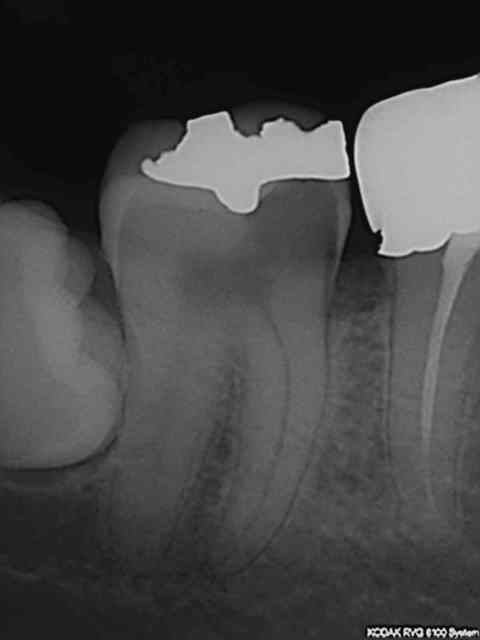

Une autre a refusé mon devis pour 2 CCM, car elle n'a que 120 € à sa charge, et ce n'est pas le problème, mais trouve que cette dépense est "somptuaire" et ne veut pas "coûter si cher à sa mutuelle". Je précise que le devis porte sur 15, fracture sous gingivale de la cuspide palatine exposant la pulpe (j'ai déjà fait l'endo), et sur 14 ( CCM hors d'âge, teinte fausse à crier et bord cervical inadapté exposant un liseré de dentine noirâtre sur 2 mm). On ne pourra donc pas m'accuser de faire du surtraitement. J'ai consenti à ne faire que 15, avec moults sourires et explications, mais elle vient d'annuler ses RV, et restera donc avec un cavit ou ce qu'il en reste sur sa 15. J'en reste perplexe.